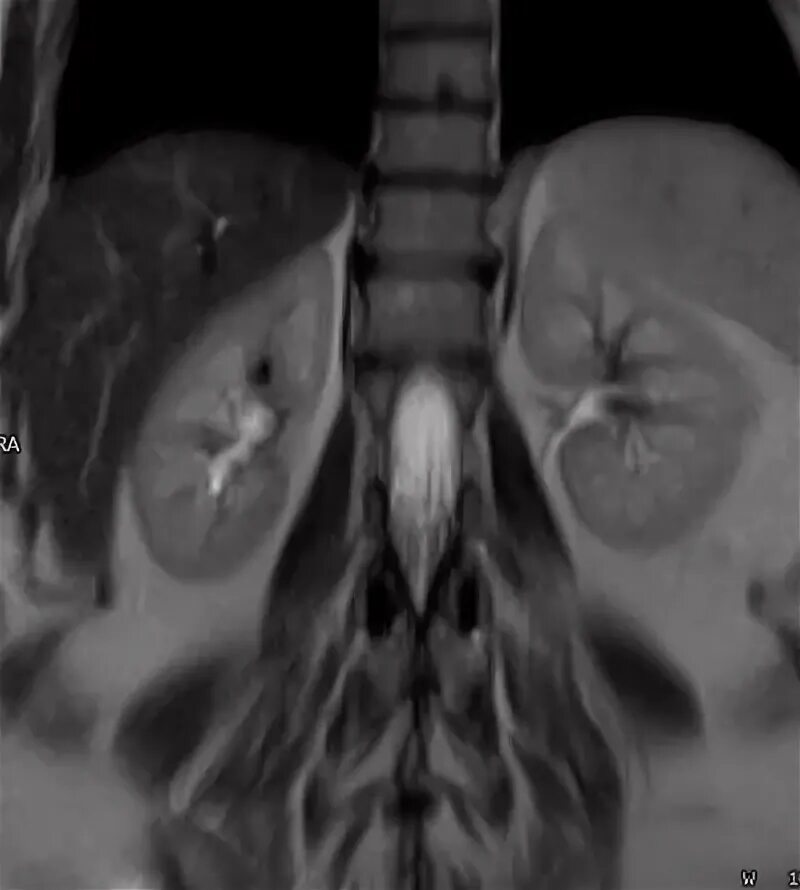

Что входит в мрт забрюшинного пространства